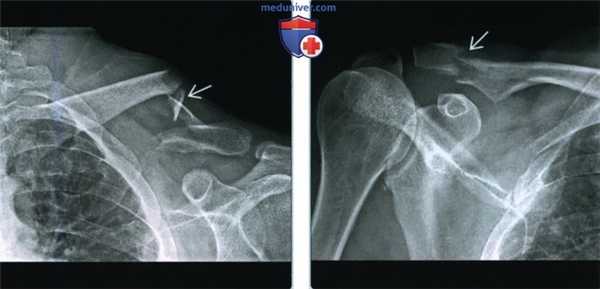

Слева) Передне-задняя рентгенограмма: молодой человек с болью после падения. Ширина акромиально-ключичного сочленения равна 12,4 мм; верхняя границы нормы составляет 6 мм. Клювовидно-ключичное расстояние нормальное, следовательно, это II тип акромиально-ключичного вывиха.

(Справа) Передне-задняя рентгенограмма: пациент с III типом акромиально-ключичного вывиха. Дистальный конец ключицы приподнят относительно акромиона и также имеется расширение между ключицей и клювовидным отростком на >50% по сравнению с нормальной стороной (не показано). (Слева) На передне-задней рентгенограмме у пациента с болью в плечевом суставе после травмы можно видеть потерю конгруэнтности акромиально-ключичного сустава, но без расширения и подъема латерального конца ключицы.